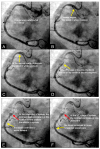

Background: In the study of coronary artery disease, the mechanisms underlying atherosclerosis initiation and progression or regression remain incompletely understood. Our research conceptualized the cardiovascular system as an integrated network of pumps and pipes, advocating for a paradigm shift from static imaging of coronary stenosis to dynamic assessments of coronary flow. Further review of fluid mechanics highlighted the water hammer phenomenon as a compelling analog for processes in coronary arteries. Methods: In this review, the analytical methodology employed a comprehensive, multifaceted approach that incorporated a review of fluid mechanics principles, in vitro acoustic experimentation, frame-by-frame visual angiographic assessments of in vivo coronary flow, and an artificial intelligence (AI) protocol designed to analyze the water hammer phenomenon within an acoustic framework. In the analysis of coronary flow, the angiograms were selected from patients with unstable angina if they had previously undergone one or more coronary angiograms, allowing for a longitudinal comparison of dynamic flow and phenomena. Results: The acoustic investigations pinpointed pockets of contrast concentrations, which might correspond to compression and rarefaction zones. Compression antinodes were correlated to severe stenosis, due to rapid shifts from low-pressure diastolic flow to high-pressure systolic surges, resulting in intimal injury. Rarefaction antinodes were correlated with milder lesions, due to de-escalating transitions from high systolic pressure to lower diastolic pressure. The areas of nodes remained without lesions. Based on the locations of antinodes and nodes, a coronary acoustic action map was constructed, enabling the identification of existing lesions, forecasting the progression of current lesions, and predicting the development of future lesions. Conclusions: The results suggested that intimal injury was likely induced by acoustic retrograde pressure waves from the water hammer phenomenon and developed new lesions at specifically exact locations.